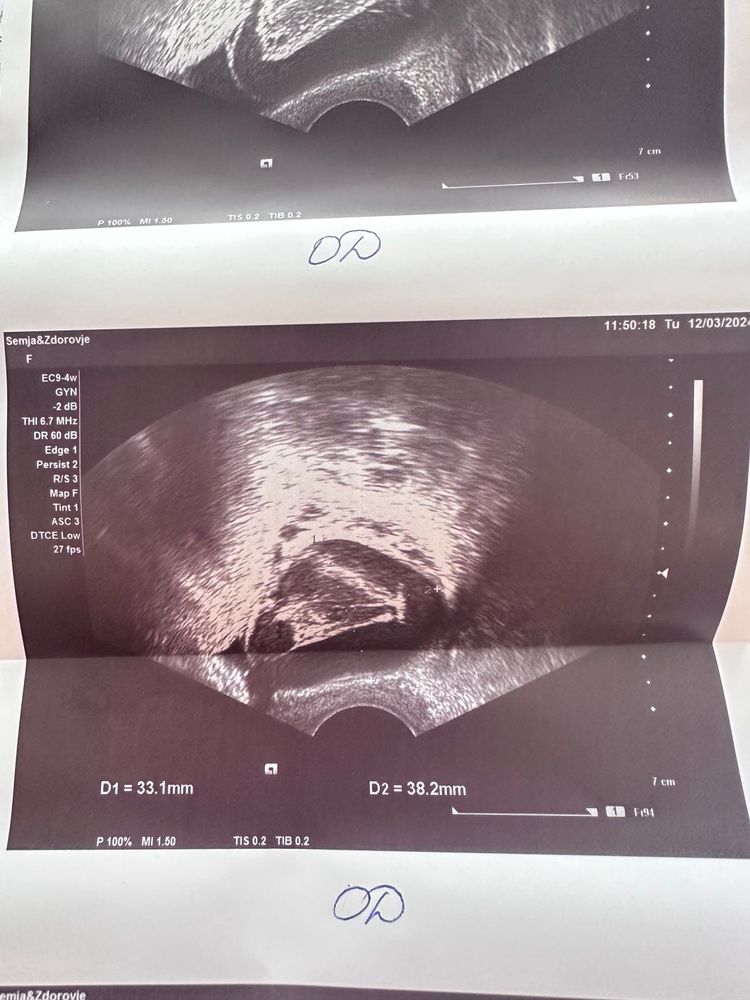

Я 2-й день пытаюсь разобраться с кистой. По узи незначительная жидкость, эндометрий секреторный 9,1 мм и киста 33х38 мм. Какая киста, мне так и не сказали. Бт странная, по ней тоже понять что-то сложно. 3 дня тесты на овуляцию были положительные.

Алина , так как самого заключения УЗИ я не вижу, основываясь на Вашем описании и снимках, с больше долей вероятности можно предположить что овуляция была с образованием кисты ЖТ, что бывает часто.

В описании УЗИ должны были указать что за киста. Основываясь на данных о секреторном эндометрии и наличии свободной жидкости, можно предположить что это киста ЖТ

Юлия , спросила может ли это быть киста желтого тела, узист пожала плечами, написано просто гипоэхогенное образование. т.е. она просто сказала "киста". Неделю назад был доминантный фолликул 16 и через пару дней полосатые тесты на овуляцию.